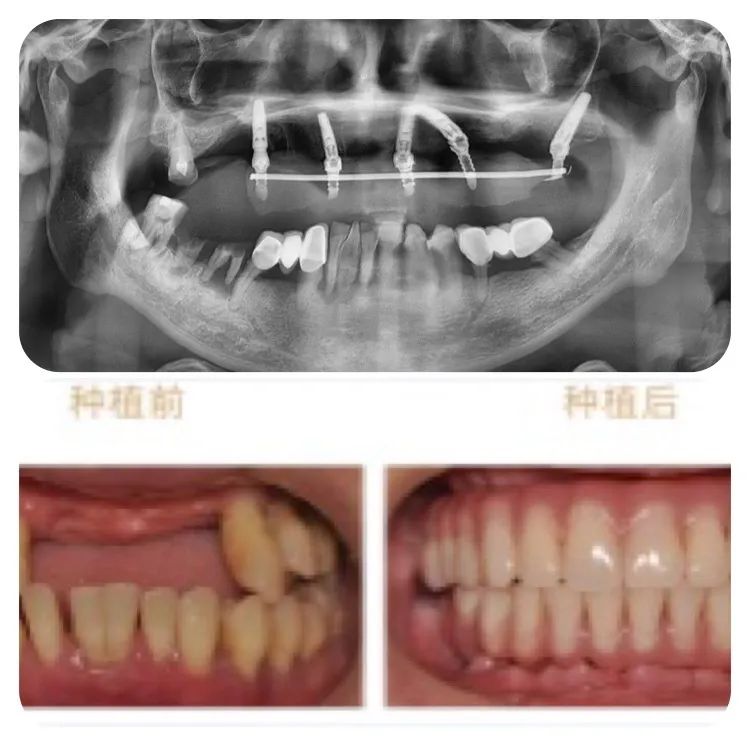

此次成功种牙的78岁高龄的老人,不但同时患有高血压、心脏病及糖尿病,口腔条件也不容乐观:因外伤引起牙缺失2年,有较严重的牙周炎,是非常典型的高龄疑难种牙案例。

针对老人的口腔条件,重庆泰康拜博口腔VIP种植工作室通过3D数字化种植设计系统为他个性化计了带1颗穿翼板种植的即刻负重种植牙方案,即拔即种,全口牙在1天之内完成了种牙、戴冠全过程,手术完成后带上临时牙冠,牙齿就已经可以正常使用。

术后1周复查,通过口腔CT检查,可以看见老人的种植牙非常精准、稳固。老人自己也描述,他在种牙的时候感觉非常轻松快速,几乎没有痛感,打个盹的功夫,牙齿就种好了。